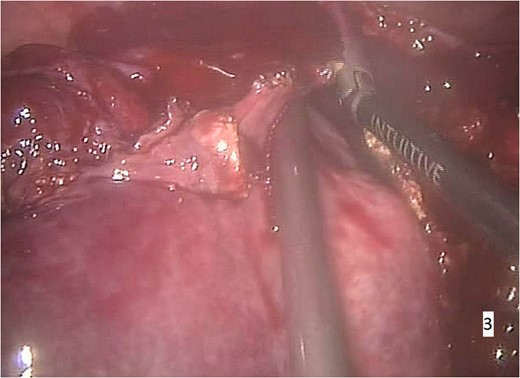

The procedure was carried out under general anaesthesia and the patient was monitored by ECG. Peripheral oxygen saturation (SpO2), end-tidal CO2 concentration and body temperature were measured throughout the whole operation. Gastric intubation and bladder catheterization were realized. A central venous line was placed and an intra-arterial catheter was positioned for continuous monitoring of the blood pressure and gas analysis. The patient was placed in supine position with parted legs in 20° Trendelenburg position. Pneumoperitoneum was achieved. A port was placed for the robotic camera and three additional ports were introduced. Cholecystectomy was first performed leading to a better optimal exposure of the hepatic hilum. Using the da Vinci surgical system, a right segmental hepatectomy was performed (Figs 3 and 4).

Intraoperative imaging. Segmental right hepatectomy and removal of the excised specimen through a small abdominal incision.